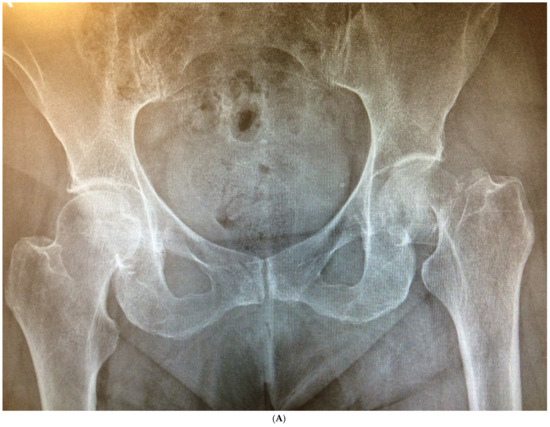

The average cup inclination and anteversion were 43° ± 3° (range, 38–50°) and 10° (range, 0–15°), respectively, in the SFS group, compared with 44° ± 5° (range, 37–50°) and 5° (range, 3–15°) in the CSS group. All acetabular components were positioned within Lewinnek’s safe zone. No radiolucent lines, cup migration, or broken screws were observed in either group throughout the follow-up period. Radiographic signs of osseointegration were present in all implants, with at least three of Moore’s criteria met in every SFS case (Figure 3A–C), indicating complete osseointegration. Similar findings were noted in the CSS group (Figure 4A–C). No femoral radiolucency or periprosthetic osteolysis was detected at any scheduled follow-up. Stem subsidence of approximately 3 mm was observed at the 3-month follow-up in two hips in the SFS group and three hips in the CSS group; however, these cases were not associated with clinical symptoms or functional impairment. No femoral stem loosening was identified during the follow-up period. A leg length discrepancy (LLD) of less than 1 cm was observed in three hips in the SFS group (average, 4 ± 3 mm) and in eight hips in the CSS group (average, 4 ± 5 mm). None of these discrepancies resulted in clinical or functional complaints, and no heterotopic ossification was identified in the radiographic evaluations (Table 4).

Figure 4.

(A) Preoperative anteroposterior X-ray. Left hip sustained a displaced femoral neck fracture. (B) Postoperative anteroposterior X-ray (CSS group). Femoral stem shows osseointegration and good proximal loading, with no bone resorption at final follow-up. (C) Postoperative lateral X-ray (CSS group). At final follow-up, the stem shows no subsidence and good fixation.